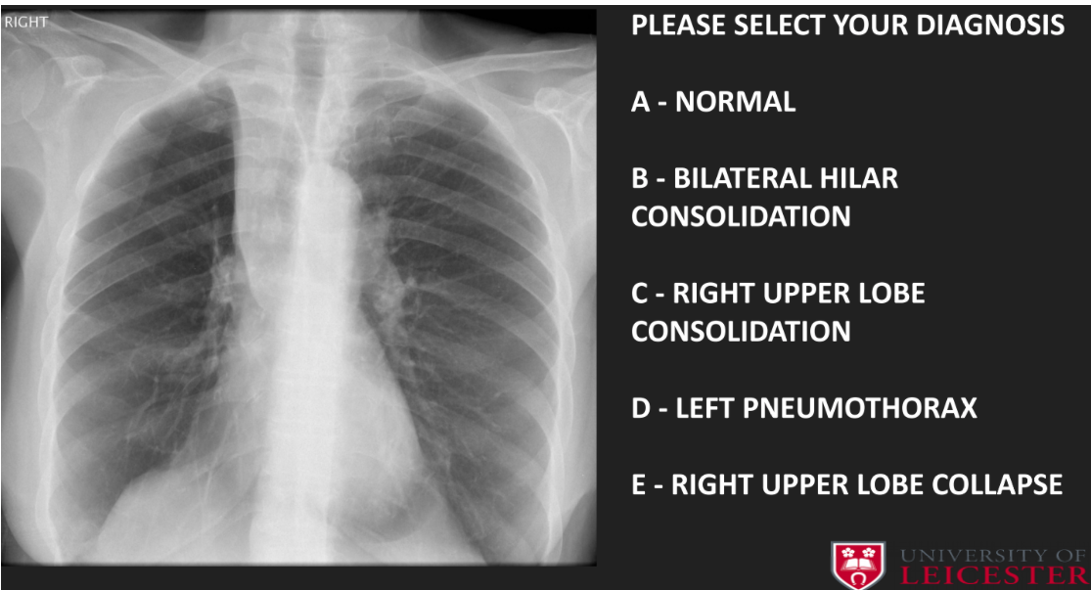

Q

diagnosed

A

C- right upper lobe collapse